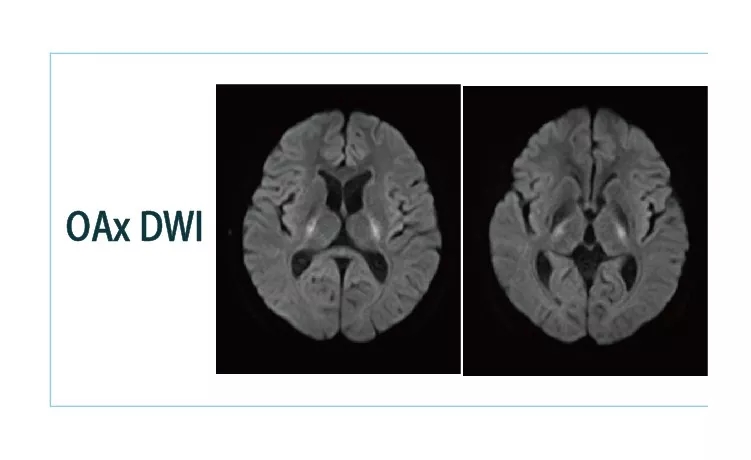

【朗润影像档案】20181130磁共振影像病例结果讨论